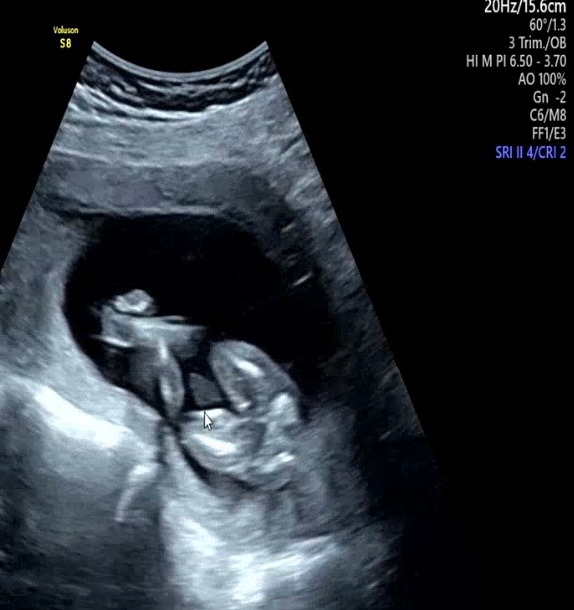

의사 선생님 왈 "공주님 이네요~"